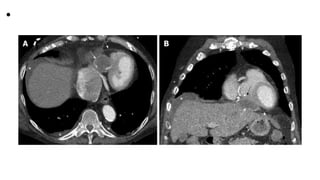

• Pericardial hydatid cyst. A, B: Axial and coronal

contrast enhanced computed tomography images

show a partially peripherally calcified cystic lesion

(white arrows) along the inferior aspect of the

heart and within the pericardial sac (dashed

arrows) with mild mass effect and displacement of

the right ventricle (black arrow). Small pleural

effusions and ascites are shown (asterisks).